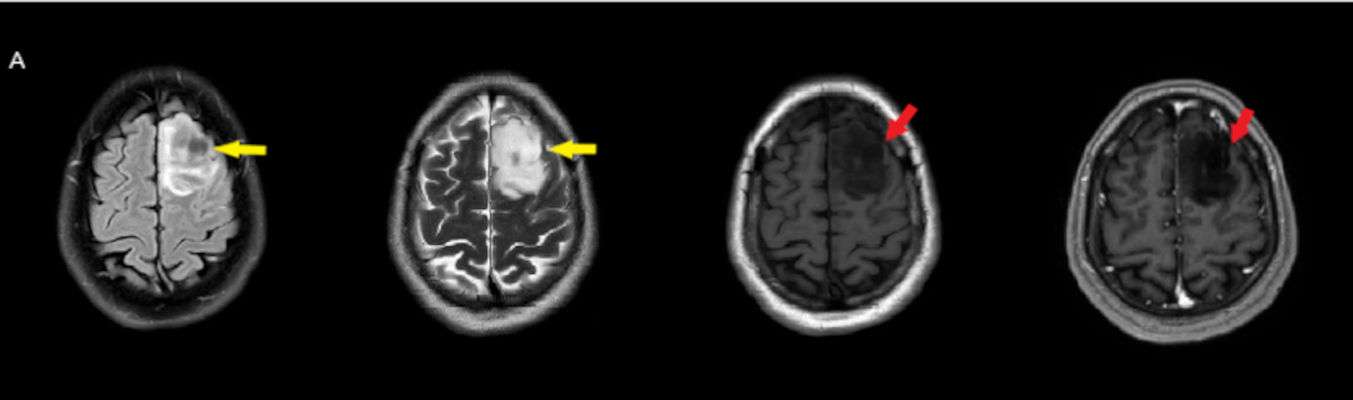

- Sol frontal kortikal-subkortikal yerleşimli aksiyel T2A görüntüde hiperintens sinyal özelliği gösteren (oklar) ve FLAIR görüntüde sinyali ağırlıklı olarak baskılanan (oklar) kitlesel lezyon izleniyor. Lezyon T1A görüntüde hipointens olup post-kontrast T1A görüntüde bu düzeyde patolojik kontrastlanma izlenmiyor (oklar).

- FLAIR’de T2’ye benzer şekilde hiperintens görünür. Ancak T2–FLAIR mismatch bulgusu, bu tümör tipi için oldukça karakteristiktir.

- T2–FLAIR mismatch bulgusu, T2AG’de homojen hiperintensite ile FLAIR görüntüde santral sinyal baskılanmasının ve çevrede hiperintens halka görünümünün bulunduğu bir fenomendir. Bu bulgu, özellikle IDH-mutant, 1p/19q kodelesyonu olmayan astrositomları tanımlamada oldukça özgül bir biomarker olarak literatürde vurgulanmıştır. Ayırıcı tanıda akla gelmesi gereken oligodendrogliomlarda T2/FLAIR mismatch bulgusu genellikle görülmez.

- Olgumuzda T2-FLAIR mismatch bulgusu mevcut olup, opere edilmiş ve tanısı histopatolojik olarak konulmuştur.